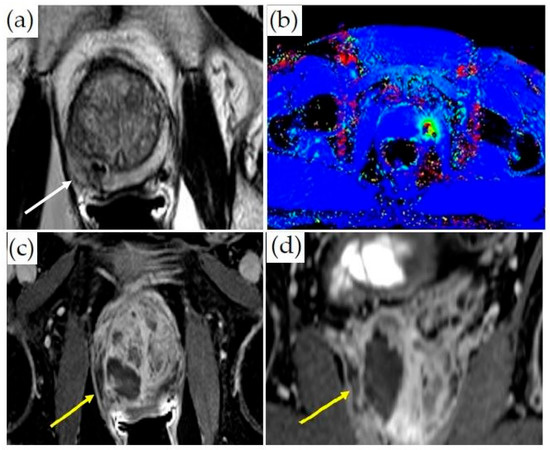

3.1.4. MRI-Guided Focal Laser Ablation